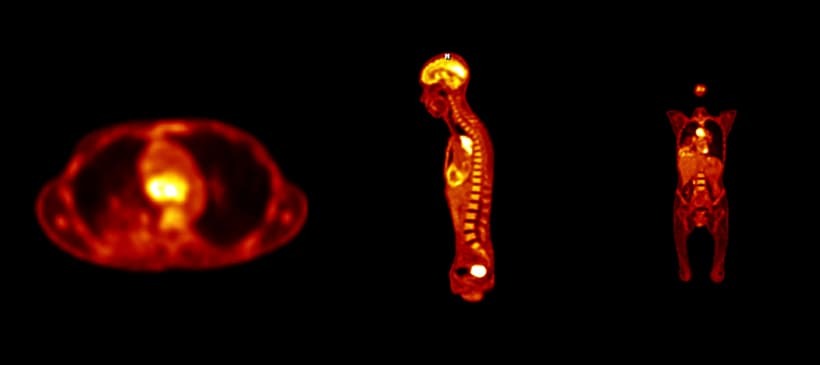

PET検査は、微量の放射線を放出する陽電子の薬剤(放射線同位元素)を静脈注射などで体内に投与し、体内に集積した部分から出る放射線をPET装置で検出して画像化します。PET検査にもっともよく使われている放射線同位元素は「18F-FDG (18-Fフルオロデオキシグルコース)」という物質で、ブドウ糖に似た性質を持っています*1。

がん細胞は正常細胞よりもエネルギーの消費が激しいという特徴があり、エネルギー源となるブドウ糖をより多く取り込みます。そのため、18F-FDGを体内に投与すると、がん細胞のある部分に多く集まります。その状態でPET検査を行い、18F-FDGが放出する放射線を検出することで、がん細胞の存在を調べる仕組みです*1。なお、確定診断は内視鏡検査やCT検査、MRI検査、細胞診なども組み合わせて行われます。

PET検査で得られる画像上では、放射線を放出している部分はほかの部分よりも明るく目立って見えるため、がんが疑わしい部分を知ることができます。また、大きさ、進行の程度も調べることができるため、がんの広がりや治療効果の判定、再発や転移を調べる際などにもPET検査が行われます。近年ではPET検査とCT検査を組み合わせ、より精密な検査が可能となった「PET-CT検査」が主流となっています*1。